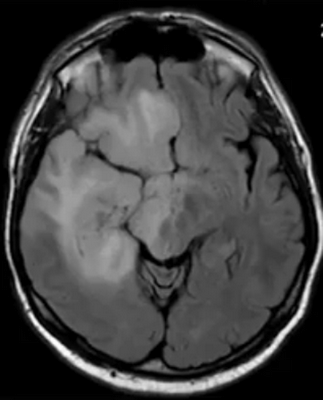

Глиобластома на МРТ головного мозга без контраста